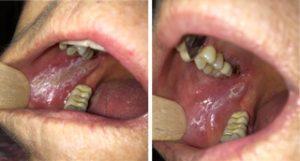

"On the market today, you will find a rinse for everything and many boast very big claims. Mouth rinses aren’t magic potions, but they can be "magical" for patients if we help them find the right rinse for their discomfort. StellaLife Inc. is one mouth rinse that could really help patients with oral pain management. The company's research claims that the formulation of its homeopathic ingredients helps with postsurgical wound healing (VEGA Oral Care Rinse), and that is is effective in the management and better healing of mucositis, aphthous ulcers, cold sores, denture sores, and nearly all other dental concerns (VEGA Oral Care Gel). " - - B. Michelle Strange, RDH, MSDH